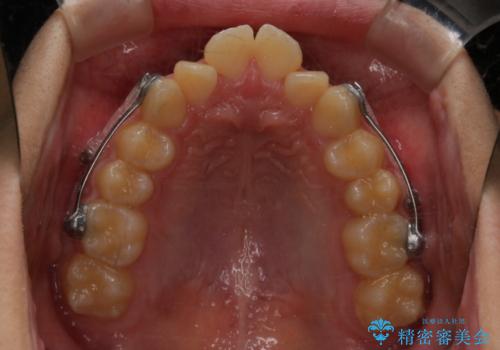

- インビザライン カリエール

よって上顎の歯を抜いて治療をするのではなく、カリエールという器具を使用して下顎を前に引っ張り出しながら上顎を引っ込めるという治療を行うことにしました。